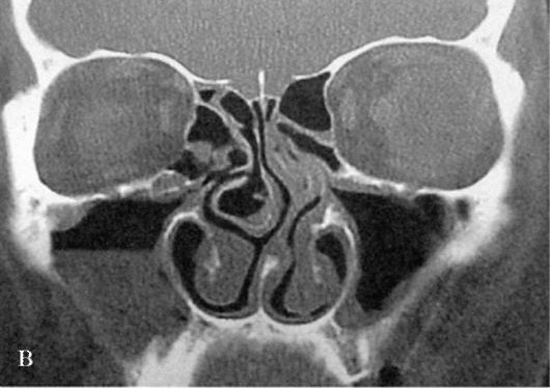

- Заблокированные дренажные пути могут быть вызваны аномалией структуры пазух носа и носовых раковин, включая искривление носовой перегородки, что может быть обнаружено при проведении компьютерной томографии (КТ).

Длительное заболевание, период усиления симптомов. В правой полости носа наблюдается накопление жидкости.